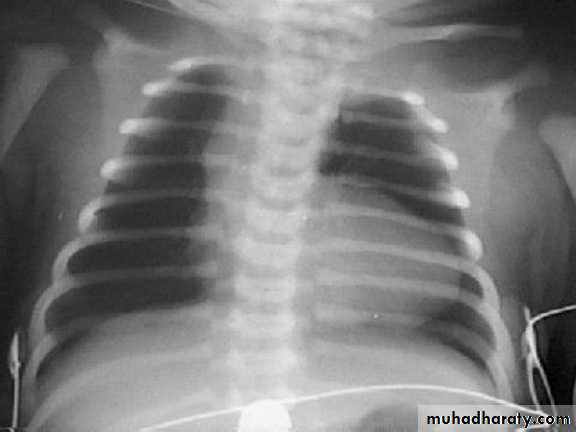

The absence of cardiomegaly on a chest x-ray usually rules out the diagnosis of heart failure.Echocardiogram assesses the heart chamber sizes, measures myocardial Function, and diagnoses congenital heart defects when present. Also measures Ejection Fraction the normal range is 55–65%.

Investigations:1. General: viral studies , elevated ESR Elevated Creatinine kinase–MB isoenzymes (CK-MB) , Lactate dehydrogenase isoenzyme 1 and Troponin I.2. CX-ray : cardiomegaly and pulmonary edema .3. MRI4. Echo5. ECG: Low-voltage QRS (< 5 mm throughout the limb leads) is the classic pattern,prolonged PR interval, ST depression and T-inversion. Sinus tachycardia, arrythmias and AV block

-Chest x-ray--cardiomegaly, pulmonary congestion.